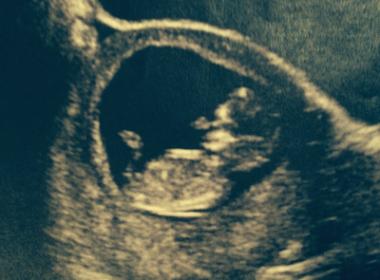

here is a picture of my 12 week ultrasound. I'm not sure if they are clear enough but guess if you can see anything thanks!

If that is the nub then I am thinking boy. But it looks very early and baby is very curled up as well!